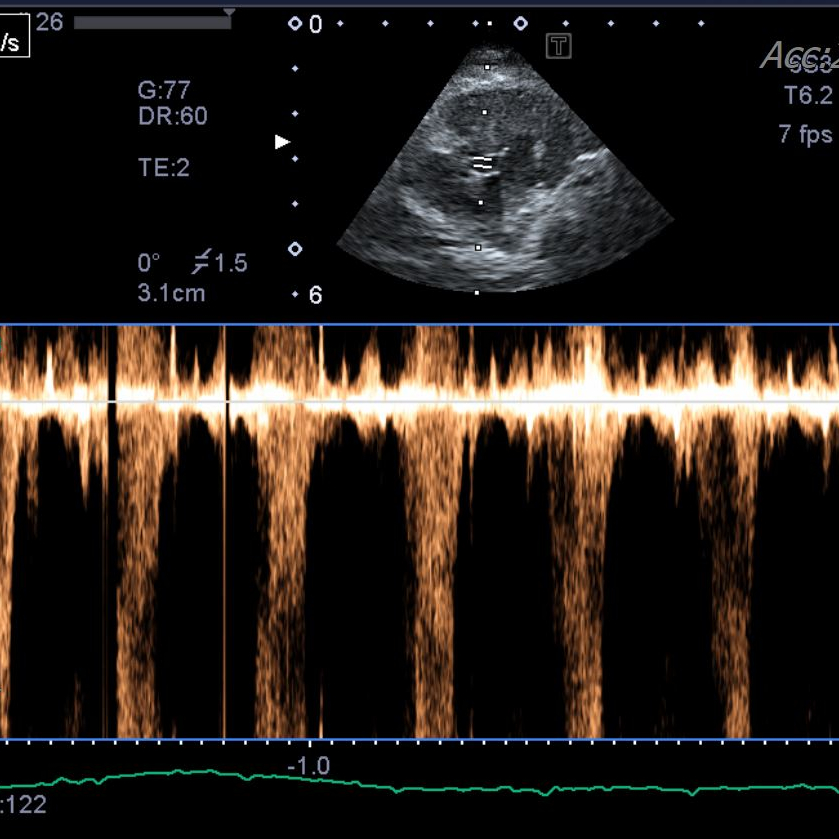

<내원 당시 환자 상태>·코리안숏헤어, 14세·갑상선기능항진증 #갑상선기능항진증 #고혈압·심근비대증(HCM)·4년차 갑상선기능항진증 #갑상선기능항진증(HCM)·4년차 갑상선기능항진증 관리 중,

내원한 환자는 주치의병원에서 4년 전 갑상선기능항진증과 심근비대증(HCM)을 진단받았고 이후 꾸준히 갑상선약, 심장약을 투약해 왔습니다.최근 환자가 다시 불안해하면서 갑상선 호르몬 수치가 다시 증가하는 것으로 확인됐습니다.갑상선약을 조정하였으나 호르몬 수치가 정상적으로 회복되지 않아 주치의와 상담 후 방사성 요오드 치료를 위해 헬릭스 동물 메디컬센터에 내원하게 되었습니다.갑상선 기능 항진증은 주로 어떤 질병인 것입니까?고양이들, 노령고양이에게 흔히 발생하는 갑상선기능항진증(갑기항)은 갑상선호르몬 과다분비가 일어나는 질병입니다.

환자는 헬릭스동물메디컬센터에 초진 내원하여 종합검사를 실시하여 현재 환자의 몸 상태와 호르몬 수치를 정확히 파악하였습니다.

- 내원 및 전신상태평가 예약을 통해 내원하면 신체검사, 혈압측정, 호르몬검사, 전해질, 소변검사, 영상검사를 실시하여 환자의 전신상태를 평가합니다.